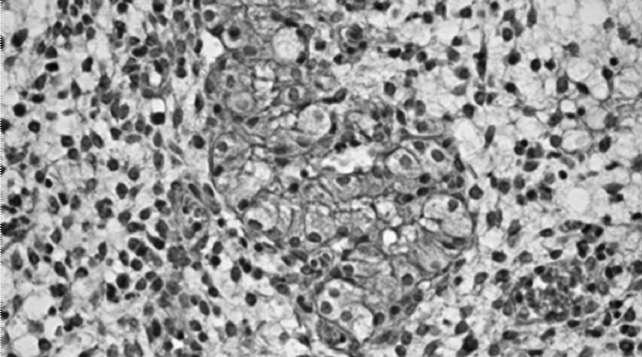

We analyzed the IHC results of a 29-year-old patient, who was admitted with primary infertility. The patient had morphologically confirmed fibroglandular polyps of the endometrium, which was previously identified by ultrasound examination.

Based on the findings of IHC analysis, ER and PR expression in the endometrium correspond to menstrual cycle phases (Figure 3). In addition, signs of chronic inflammation (i. e., chronic endometritis) with a weak autoimmune component (Figures 4-10) are revealed.

Fig. 4. Focal lymphocytic and neutrophil infiltration of the endometrial stroma at 400× magnification

Fig. 5. Vacuolar dystrophy of gland epithelium and endometrial stroma at 1,000× magnification